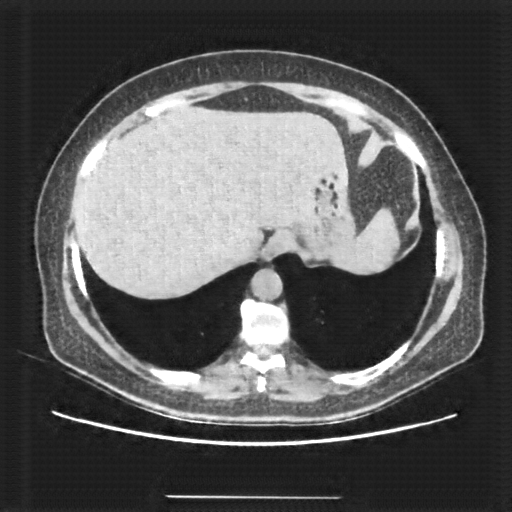

Generated VENOUS CT scan (A→B translation)

Full window (WL 1023.5, WW 4095 β†’ Low βˆ’1024, High +3071)

Actual HU range: [-1024.0, 838.3]